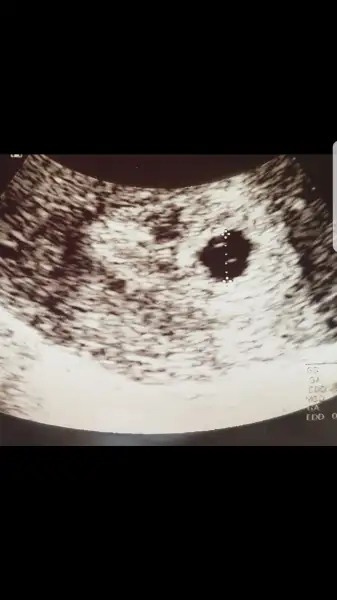

- 8 Mart 2015

Ben sen uzun süredir imom kullanıyordum hamile olduğumu öğrendim dr imoma devam dedi..

ben hamile kalmadan önce Imom kullanıyordum